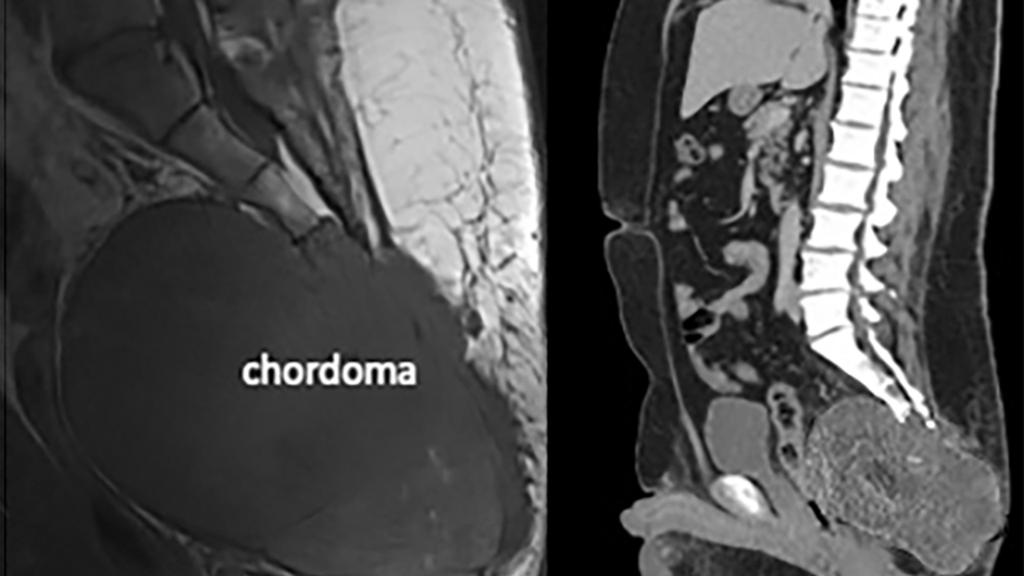

Imaging of a large sacral chordoma

Figure 1: Large sacral chordoma involving the sacrum and coccyx.

Mr. V, a 41 year old patient was referred to the Emergency Room at the Hospital of the University of Pennsylvania (HUP) after a CT scan at his community hospital revealed a large mass at his sacrum (Figure 1). In the three years prior to this event, he had experienced progressive pain at his sacrum and coccyx, with a significant effect on his daily life.